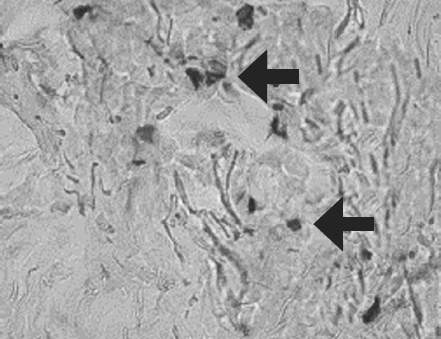

Histological examination of biopsy samples taken from the area of ATMSC transplantation for all the patients revealed the presence of pronounced vascularization with the perifocal proliferation of fibroblasts in both the superficial and deep layers of the dermis (Fig. 6, 7). An immunohistochemical study revealed that the use of ATMSCs resulted in a 5.6-fold increase in the expression of proliferation markers of epithelial and connective tissue cell lines in the injection area (p < 0.01) (proliferation 2.1–2.2), and that apoptotic activity was completely suppressed (Fig. 8, 9). Laser Doppler flowmetry assessment of the microcirculation in the area of stem cell injection on day 7 after early necrectomy, skin grafting, and the administration of MMSCTM showed double the average level of perfusion and mean square deviation of the amplitude of blood flow oscillations than for areas where MMSCTM was not used (p < 0.05) (Table 6).

Fig. 6. Patient D., 34 year sold, 5th day of observation. Active marginal epithelization. A wide band of the forming epidermal layer. Color in gof hematoxylin-eosin. Zoom ×400

Рис. 6. Пациент Г., 34 года, 5-е сутки наблюдения. Активная краевая эпителизация. Широкая полоса формирующегося эпидермального слоя. Окраска гематоксилином и эозином. Увеличение ×400